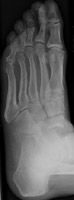

- Click on the image for a larger versionBOblique radiograph of the ankle. There is uncovering of the talus, due to dislocation.